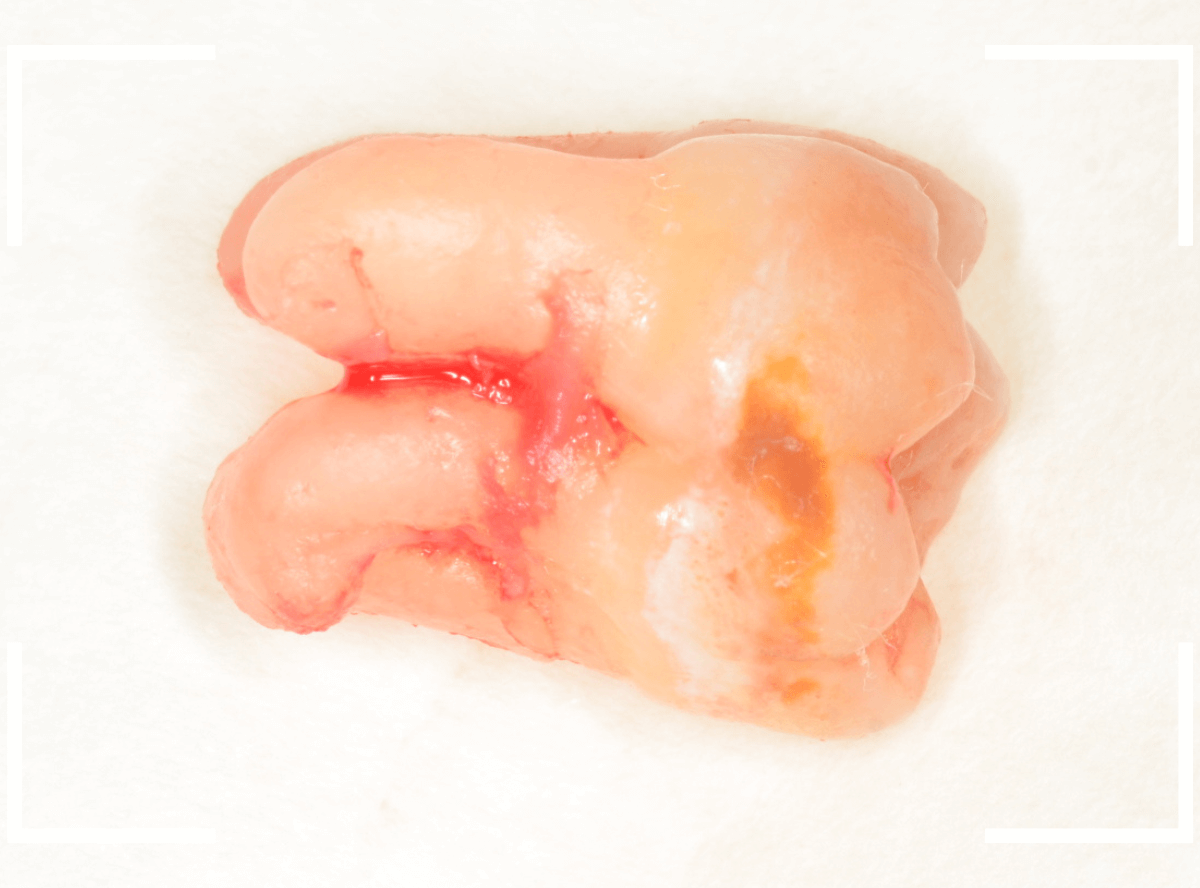

ここでは、比較的簡単なおやしらずの抜歯の例を中心にご紹介します。

このようなおやしらず、あなたはありませんか?